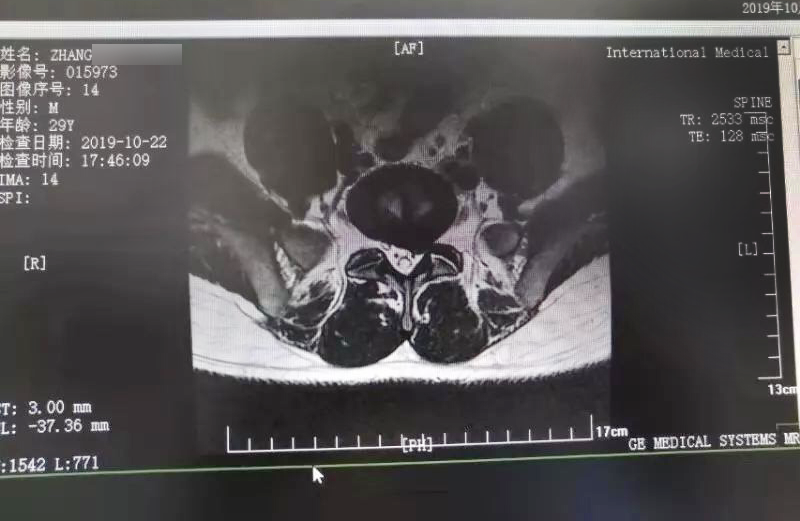

三秦網報道—西安國際醫(yī)學中心骨科醫(yī)院成功完成首例椎間孔鏡手術

三秦網報道—西安國際醫(yī)學中心骨科醫(yī)院成功完成首例椎間孔鏡手術。點擊閱讀。